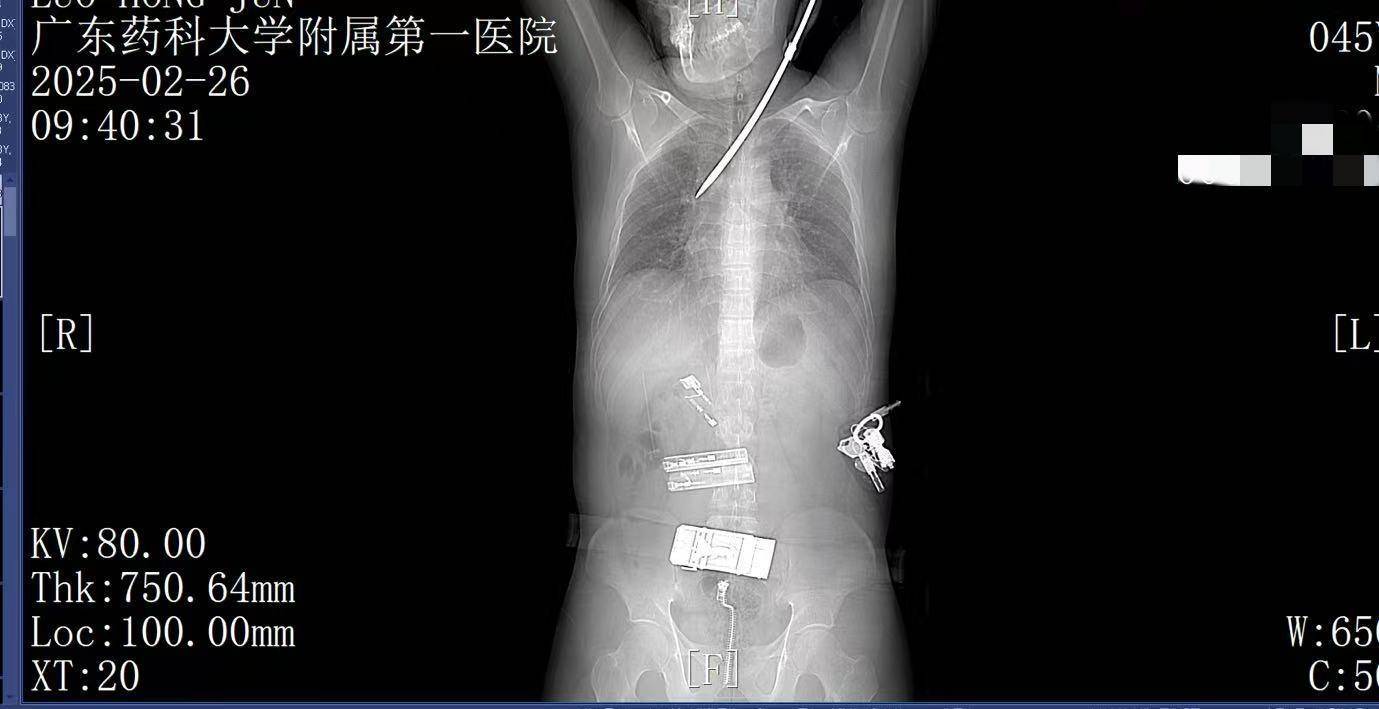

2月26日上午9时许,44岁的电梯工人罗师傅(化姓)正在广州某工地弯腰工作,突然一把螺丝刀从20多米高处坠落,刺中罗师傅的胸背部原油预处理。罗师傅当即疼痛难忍,呼吸困难。工友立即呼叫120。一场惊心动魄的生死救援立即展开。

9:22,广东药科大学附属第一医院救护车到达现场,查看患者伤情后,黄业君主治医师立即固定好螺丝刀,避免再次移动损伤神经血管,并马上电话联系医院后方,医院急诊科主任曾育辉立即通知心胸外科、脊柱外科等相关科室紧急会诊原油预处理。

9:39,救护车到达医院大门,院内急救团队已经做好准备原油预处理。在紧密监护的情况下,全程采用绿色通道。到达医院时,罗师傅已经面色苍白,呼吸急促。螺丝刀已深深刺入罗师傅右肺,随时可能因大出血而危及生命。

9:41,快速完成头+胸+腹部CT检查,经多学科会诊,明确螺丝刀异物刺入肺部原油预处理。CT显示螺丝刀紧贴肋间血管、上肺后段动脉,尖端距右肺门仅2厘米,一旦贸然拔出螺丝刀,极有可能引发大出血,导致失血性休克甚至死亡,必须紧急手术。

9:50,收入心胸外科急诊手术治疗原油预处理。30分钟内即完成检查抢救处置。

无影灯下,麻醉科陈建颜主任团队精准实施单肺通气保障氧合,心胸外科肖海平主任团队沉着冷静,采用单孔胸腔镜技术进入胸腔,一步步地分离受损组织,仔细止血,避开重要血管原油预处理。医护默契配合,成功将插入患者体内达13厘米的螺丝刀完整取出。手术顺利完成,罗师傅的生命体征逐渐恢复平稳,成功脱离了生命危险,大家心里悬着的石头终于落地。